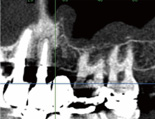

2.金属の影響を受けずに骨の状態を把握

金属はX線を通しにくいため、従来のCTでは口腔内の金属(歯の詰め物や冠)の影響で周りの骨の状態が把握できないことがありました。

当院では金属の影響を除去するプログラムにより、金属の周りでも骨の状態を診断することができます。